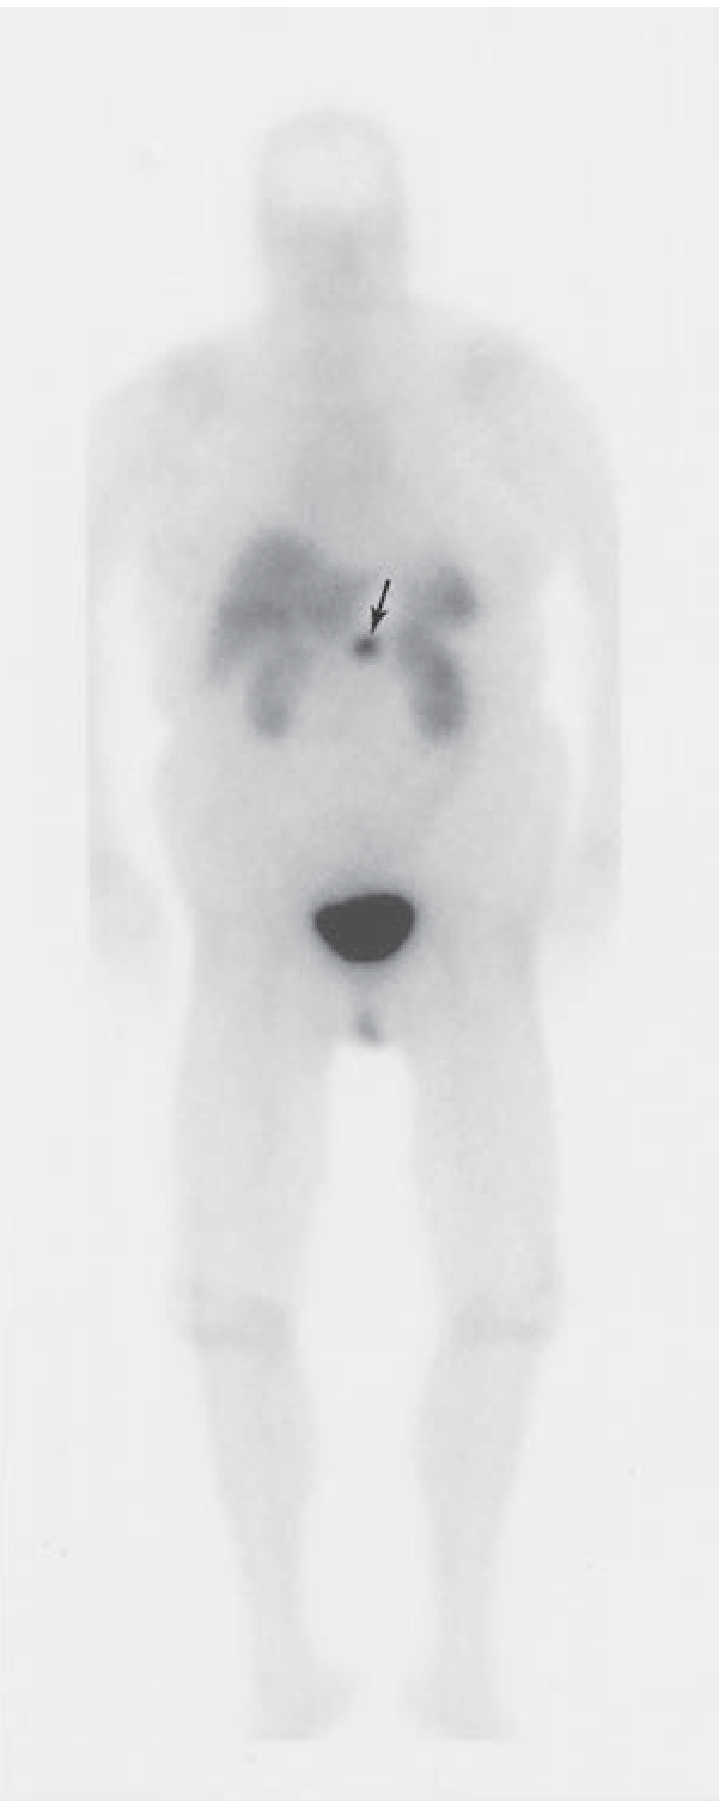

| Ga-68 DOTATATE PET scan (somatostatin receptor imaging) | Not routine — use if metastases suspected or tumor occult on other imaging |

If occult: Ga-68 DOTATATE PET or arterial calcium stimulation/venous sampling